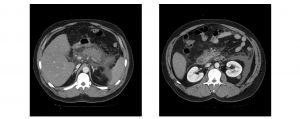

Ante estos signos de irritación peritoneal se decide realizar un TAC abdominal donde se observa pancreatitis aguda necrótica, visible incluso sin infundirse contraste. También es visible un defecto de repleción en la vena mesentérica superior y esplénica compatible con trombosis, pero sin identificarse colecciones intraabdominales.

Se repite el TAC abdominal en el que se observa pancreatitis aguda con colecciones necróticas peripancreáticas agudas, con necrosis glandular, y una trombosis venosa previa sin cambios con respecto a la primera prueba.

Este TAC muestra pancreatitis con necrosis pancreática y peripancreática pero sin nuevas complicaciones. Lo que sí se observa es el infarto esplénico, que ya se visualizó tras la trombosis de la vena esplénica.